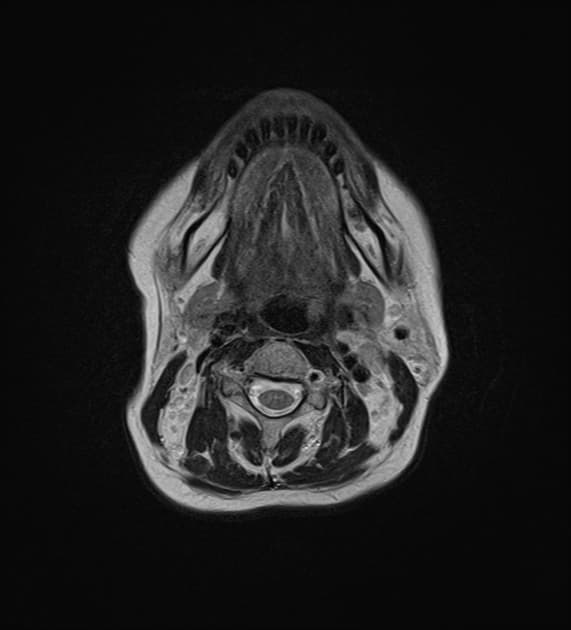

- Hiện tượng chèn ép vùng trán của vòm sọ (calvarium) tạo nên hình dạng giống quả chanh ở sọ.

- Tiểu não có hình dạng cong như quả chuối do hố sau nông.

- Hai hình ảnh này là những dấu hiệu điển hình gợi ý dị tật hố sau nông hoặc bất thường kiểu Chiari (Chiari malformation).

Trường hợp này thể hiện những đặc điểm dễ nhận biết trên các mặt cắt ngang tiêu chuẩn trong chụp hình thai nhi, gợi ý một dị tật ống thần kinh như bất thường kiểu Chiari (Chiari malformation).

Một cách so sánh sinh lý học giúp ghi nhớ cơ chế của bất thường kiểu Chiari là: hộp sọ dường như đang cố đẩy mô não ra khỏi lỗ chẩm (foramen magnum) bằng cách chèn ép từ phía trước (tạo dấu hiệu chanh), đồng thời nén ép hố sau từ phía sau, dẫn đến hiện tượng đẩy các nhân hạnh nhân (amygdala) hoặc thân não ra ngoài lỗ chẩm. Cơ chế này tạo nên dấu hiệu chanh (lemon sign) và dấu hiệu chuối (banana sign).

- "Dấu hiệu 'chanh' là hiện tượng lõm ở vùng trán vòm sọ thai nhi, thường thấy ở tam cá nguyệt thứ hai, liên quan đến dị tật ống thần kinh hở."

- "Dấu hiệu 'chuối' mô tả hình dạng cong bất thường của tiểu não do chèn ép và thoát vị trong hố sau nhỏ."

- "Hai dấu hiệu siêu âm này gợi ý mạnh đến bất thường Chiari loại II, thường đi kèm với nứt đốt sống có thoát vị màng - tủy."

Dấu hiệu chanh và chuối là những hình ảnh điển hình trên siêu âm trước sinh, liên quan đến bất thường Chiari loại II, thường gặp trong bối cảnh nứt đốt sống có thoát vị màng - tủy. Dấu hiệu 'chanh' – hiện tượng lõm ở vùng trán vòm sọ – xảy ra do giảm áp lực nội sọ do rò dịch não tủy tại vị trí dị tật ống thần kinh hở, dẫn đến sụp vào trong của các xương sọ đang phát triển. Dấu hiệu 'chuối' phản ánh hình dạng biến dạng, kéo dài của tiểu não khi bị chèn ép và thoát vị vào hố sau nhỏ hoặc nông. Mặc dù đôi khi các dấu hiệu này có thể xuất hiện ở thai bình thường trong giai đoạn sớm, nhưng nếu tồn tại sau 24 tuần thì rất gợi ý một dị tật ống thần kinh nghiêm trọng. Việc phát hiện trước sinh giúp lên kế hoạch đa chuyên khoa, can thiệp tiền sản và quản lý phù hợp quanh thời điểm sinh.